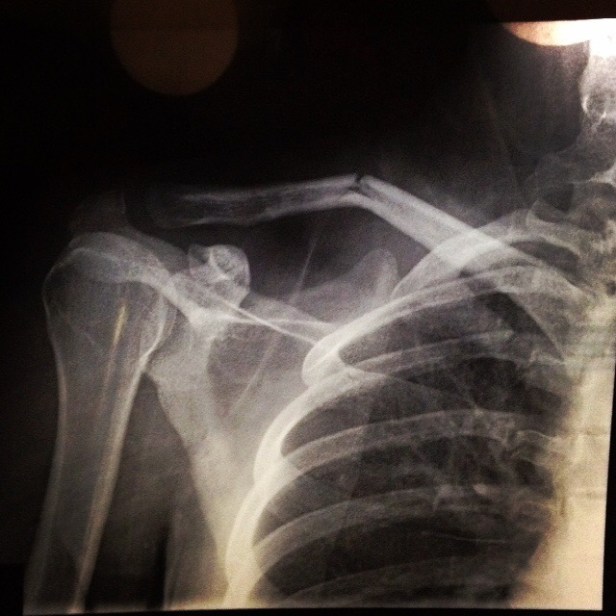

Tuesday: Dad takes Adelaide to Minor Injuries who xray and confirm broken collarbone

So I have to try GP again on Monday.. (Luckily? I know that x-ray is always going to have a broken bone on it)